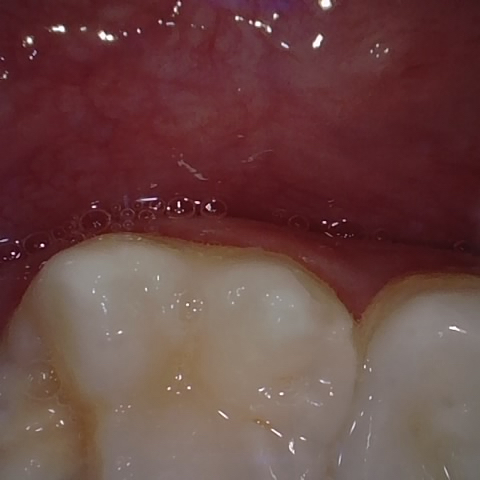

Annotated as "Bad"